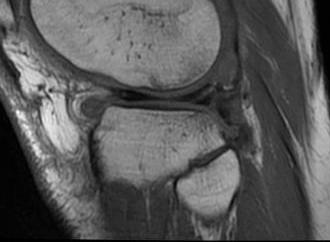

- used arthroscopy as gold standard to see if healed or failed repair

- MRI 90% sensitive, but up to 98% specific